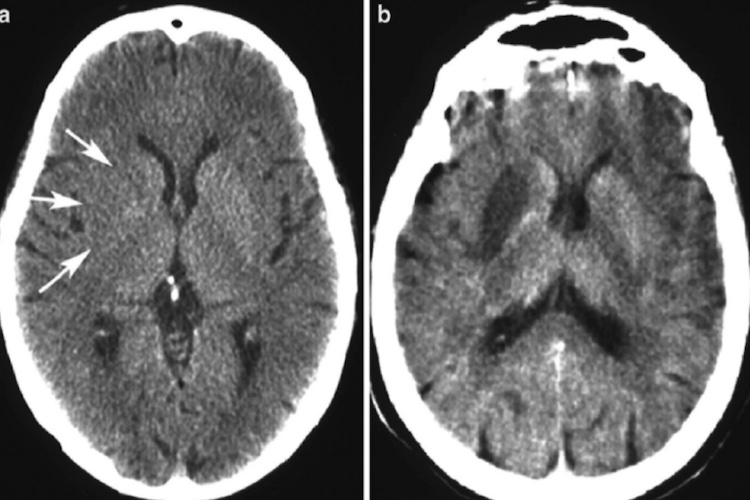

缺血性梗死:CT平扫,在发病24小时内常难以显示病灶;4小时后表现为低密度灶,部位和范围与闭塞血管供血区一致,皮髓质同时受累,多呈扇形,可有占位效应,但相对较轻;增强扫描,发病当天灌注成像即能发现异常,表现病变区脑血流量明显减低;其后普通增强可见脑回状强化。1~2个月后形成边界清楚的低密度囊腔,且不再发生强化。

出血性梗死:常发生在缺血性梗死一周后,CT平扫呈低密度脑梗死灶内,出现不规则斑点、片状高密度出血灶,占位效应较明显。